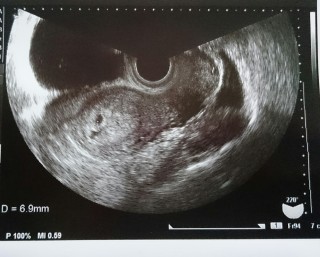

二人目妊娠。三週くらいからムカムカして生理予定日前日に検査薬で陽性反応。ずーっと下腹部が痛くて不安になり早めの4w4dで病院に行ったけど確認できず、5w0dで確認できました! 6.9mmですっ!でも下の黒い影が出血らしく安静にと言われてしまいました。次は2週間後の心拍確認!無事に大きくなってね!